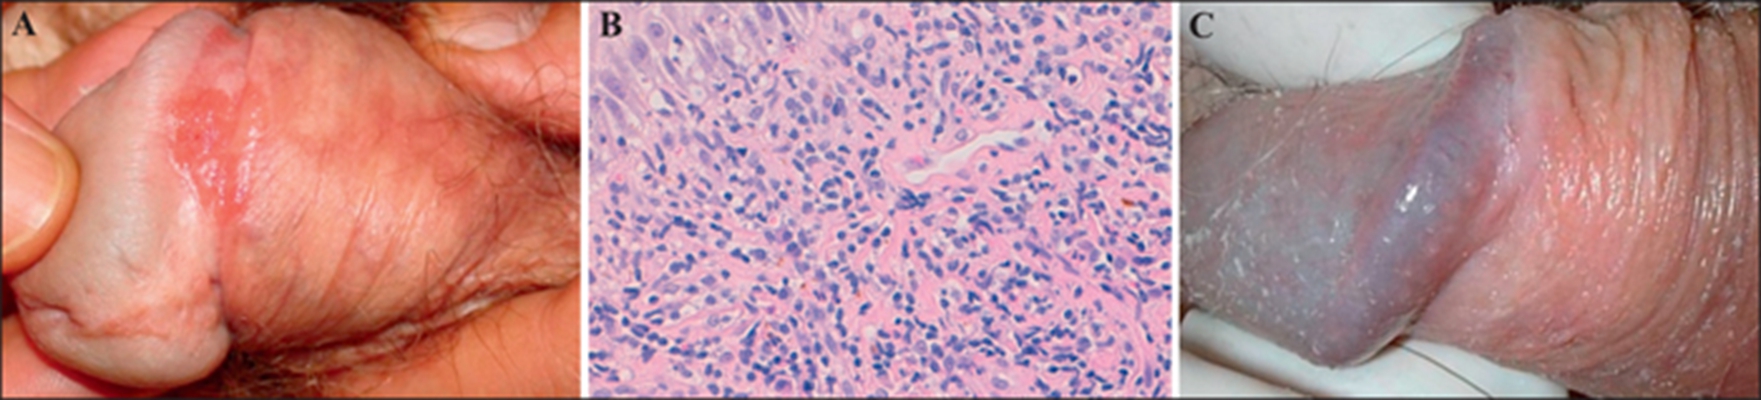

龜頭炎圖片

黴菌性龜頭炎 (48)

黴菌性龜頭炎 (49)

黴菌性龜頭炎 (5)

黴菌性龜頭炎 (50)

黴菌性龜頭炎 (8)

黴菌性龜頭炎 (9)

黴菌性龜頭炎 (42)

黴菌性龜頭炎 (43)

黴菌性龜頭炎 (26)

黴菌性龜頭炎 (27)